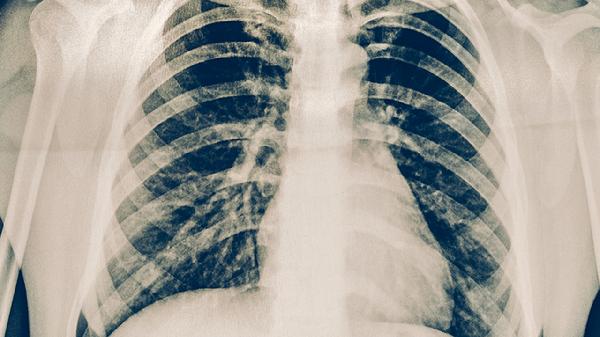

2、复查影像学

需立即进行胸部CT检查明确肺部病灶变化,若发现活动性结核病灶需重新评估痰菌情况。胸片联合B超可判断是否存在胸腔积液,CT增强扫描能鉴别胸膜增厚与肿瘤复发。影像复查频率应根据疼痛程度调整为1-2周一次。